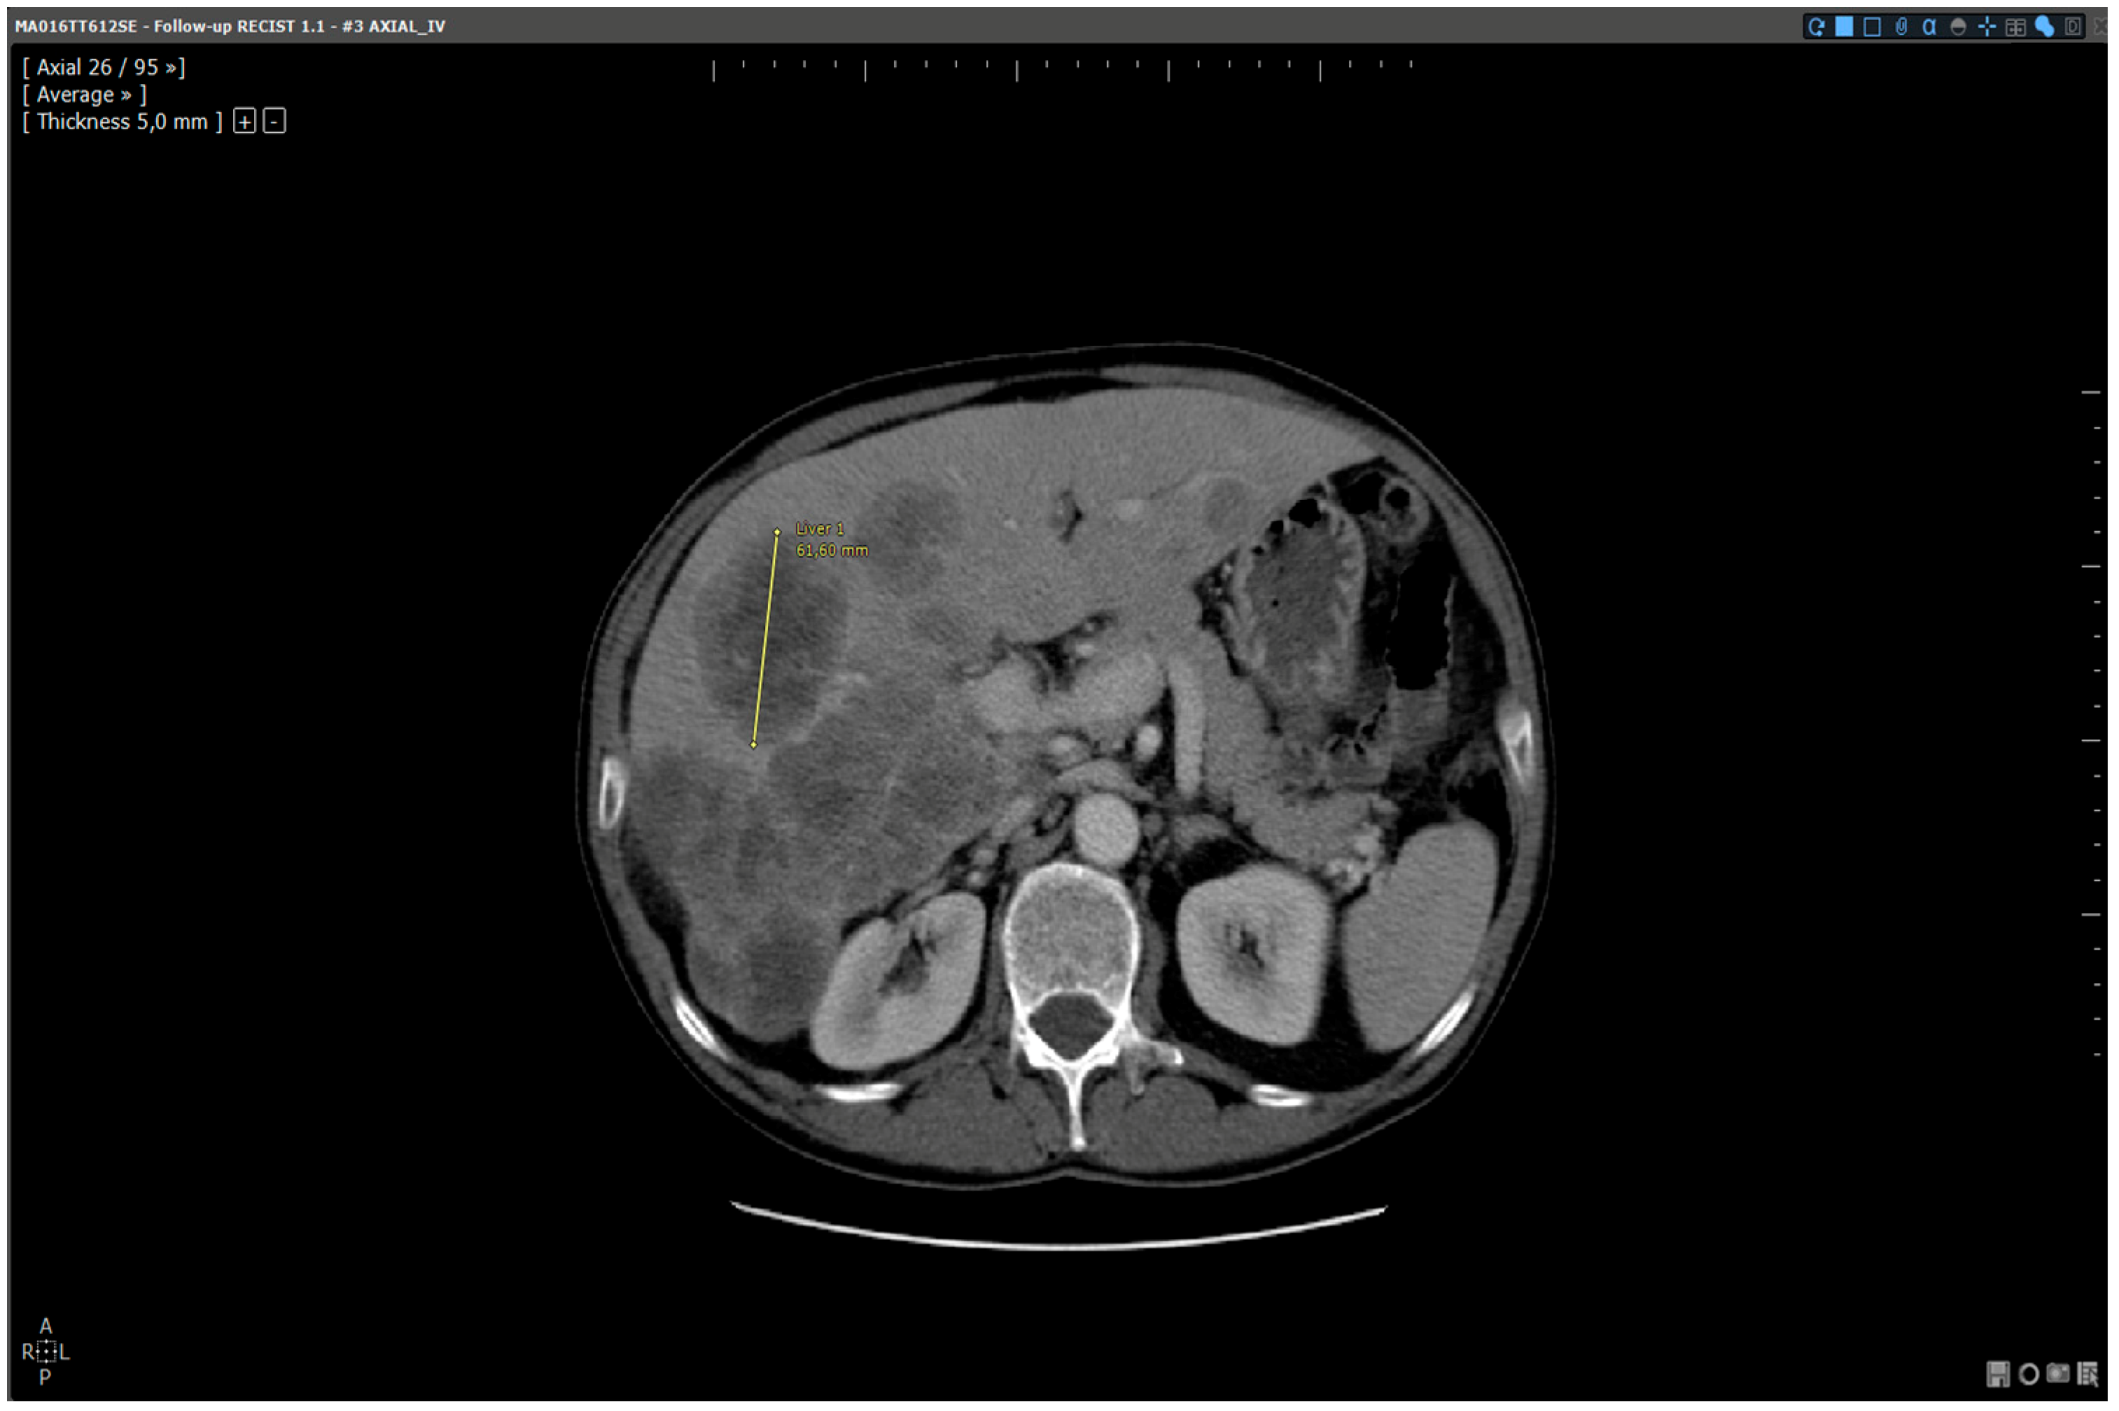

- 3D target matching technology to facilitate lesion localisation in the follow up study.

| Step 3 | Target localisation on baseline study | Manual | Automated |

| Step 4 | Target localisation on follow up study | Manual | Automated |